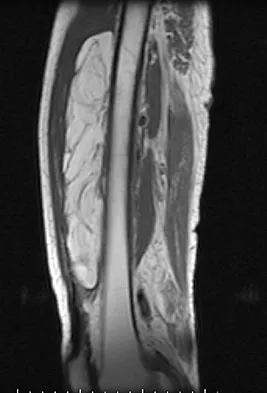

Figures 13a and 13b show the MRI scans of a 70-year-old patient who has a posterior calf mass. Examination reveals that the mass extends to the midcalf level. A biopsy specimen reveals a high-grade soft-tissue sarcoma. Metastatic work-up shows no lesions. Management should consist of

Soft-tissue sarcomas generally are treated with radiation therapy and wide surgical resection. In this patient, involvement of most of the posterior calf compartment and circumferential involvement of the posterior tibial and peroneal neurovascular bundle makes limb salvage impractical. Any attempt at wide surgical resection would leave a poorly functioning limb with questionable surgical margins. A high below-knee amputation would be the best option. Radiation therapy alone is contraindicated. Lindberg RD, Martin RG, Romsdahl MM, et al: Conservative surgery and post-operative radiotherapy in 300 adults with soft tissue sarcoma. Cancer 1981;47:2391-2397. Sim FT, Frassica FS, Frassica DA: Soft tissue tumors: Diagnosis, evaluation, and management. J Am Acad Orthop Surg 1994;2:202-211.